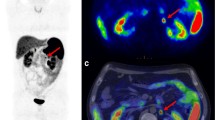

Among the 6 patients presenting lymphnodal involvement at histological examination, 68Ga-DOTATOC PET/MRI identified only 1 patient having lymphnodal involvement, not showing any 68Ga-DOTATOC uptake (Fig. 2); specifically, on MR images, a lymphnodal metastasis was identified in the right paracaval region (maximum diameter: 24 mm). Histological examination reported a pT3 pN1 G1 PanNET.

68Ga-DOTATOC PET/MRI performed for PanNET staging. A 52-year-old patient underwent 68Ga-DOTATOC PET/MRI. Axial Lava Flex MR images showed a lesion in the pancreatic head (a, red arrow), not showing any pathological uptake on 68Ga-DOTATOC PET (b) and PET/MR (c, red arrow) images. A pathological right paracaval lymph node was also detected on axial Lava Flex MR images (d, yellow arrow), not presenting pathological uptake on 68Ga-DOTATOC PET (e) and PET/MR (f, yellow arrow) images